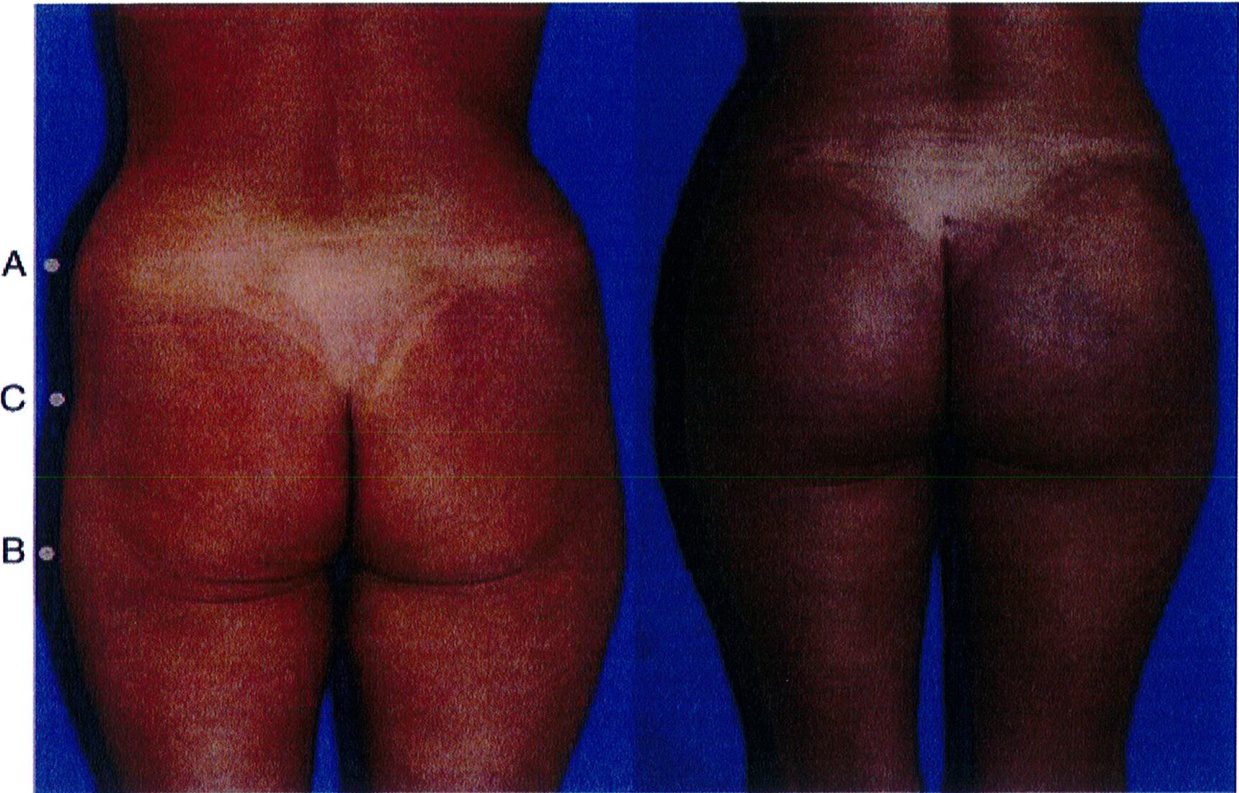

Từ góc nhìn sau – trước

Hãy tưởng tượng cơ mông nằm trên khung chậu với trục đối xứng là đường liên mông. Theo lý thuyết, cơ mông có khối lượng bằng nhau ở hai bên và có hình dạng của 1 quả bóng đá. Để đánh giá kỹ hơn, vẽ một đường nằm ngang (Hình 18). Điều này cho phép chia mông thành 4 góc phần tư: trên trong, trên ngoài, dưới trong và dưới ngoài. Vòng mông lý tưởng là vòng mông phân bố đểu tổ chức ở 4 vùng trên. Khi đánh giá từ góc nhìn sau trước, mỗi góc trong số 4 góc này phải được đánh giá xem chúng bằng nhau hay thiếu so với các góc còn lại như thế nào.

Mặt bên vùng mông có thế được chia thành 3 vùng: trên, giữa, dưới (xem hình 19). Sự phân chia tương ứng với 3 điểm A, B, C và chúng giúp xác định vùng nào được phân bố mỡ nhiều/ít hơn các vùng còn lại. Trong thấm mỹ vùng mông, phần lớn mô mỡ dưới da sẽ nằm ở vùng trung tâm (chính giữa mông), và phần mỡ dưới da còn lại sẽ được phân bố đồng đều ở hai bên. Như vậy chúng ta có thể tưởng tượng ra hình dạng tổng thể của mông khi nhìn từ phía bên là hính chữ C ngược (Hình 19). Có một số tác giả cho rằng điểm nhô ra nhiều nhất của vùng mông sẽ là điểm nằm ngang với xương mu ở tư thế đứng.

Khi làm việc từ góc nhìn bên này, chúng ta cần rõ ràng xác định được đâu là ranh giới vùng mông trên giữa dưới (Hình 20). Việc xác định này rất quan trọng nhằm

ở những bệnh nhân thuộc lớp này, hầu hết phần mông nằm ở tập trung ở giữa, mô mỡ dưới da được phân bố đều ở phần mông trên và mông dưới. Ở mặt bên, không phát hiện tình trạng sa hoặc các vết lõm trên bề mặt, bờ mông có hình chữ C mềm mại. Lớp A này là hình dáng lý tưởng cho vùng mông, đặc biệt có tính thẩm mỹ cao khi nhìn từ phía bên. Những bệnh nhân thuộc lớp này chỉ cần thực hiện thủ thuật nâng mông đơn thuần.

Trong lớp C, da không bị xệ xuống dưới nếp lằn mông nhưng nếp này cũng không được nhìn thấy rõ ràng. Mỡ phân bố đều khắp mông khi nhìn từ phía bên. Phẫu thuật làm đầy mông nên được chỉ định cho những bệnh nhân này.

Lớp B

Về cơ bản, các bệnh nhân ở lớp B có hình dáng mông điển hình như sau: không có phần da chùng xuống phía dưới nếp lắn mông, nhưng có sự xuất hiện các vết lõm ở nửa dưới của phần trung tâm, dẫn tới bờ mông không có đường cong mềm mại (Hình 27). Đối với bệnh nhân thuộc lớp này, nên phối hợp thực hiện Nâng mông với cấy mỡ tự thân. Implant cũng giúp ích trong một số trường hợp. Việc chuyển mô mỡ từ vùng này qua vùng khác có thể được thực hiện ngay tại thời điểm phẫu thuật hoặc được coi như giai đoạn 2 của phẫu